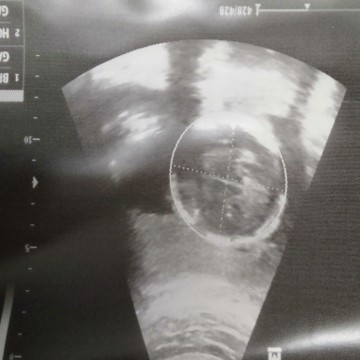

แบบนี้ผู้หญิงหรือผู้ชายคะแม่ๆพอดีน้องหนีบขาเรยมองไม่เหนคะ. #ในรูปมองไม่ออกเรยคะแต่น่าจอหมอมองเหนแขนและรำตัวแร้วคะ

ภาพนี้ไม่ชัดเลยค่ะ ดูไม่รู้เรื่องเลย

แล้วหมอบอกผู้หญิงหรือผู้ชายคะ